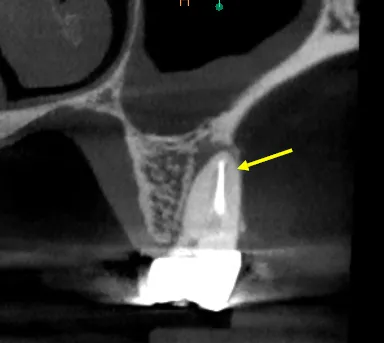

Severely calcified MB2 canal not located during initial treatment—CBCT showed complete sclerosis

The referring dentist had completed what appeared to be adequate endodontic treatment two years prior, but the patient continued to experience intermittent discomfort and sensitivity to percussion. Clinical examination revealed no obvious defects, but CBCT imaging told a different story: a completely calcified MB2 canal with associated periapical pathology.

Calcification of this severity requires a systematic approach. We used CBCT data to precisely locate the canal orifice, then employed ultrasonic tips to create a troughing pathway through the sclerotic dentin. Micro-openers (size 06 and 08) were used to negotiate the calcified canal under high magnification.

• CBCT Analysis: Identified exact MB2 location and depth of calcification